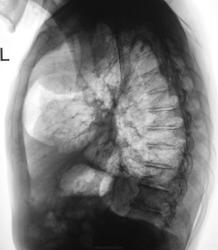

Валентин Львович, либо чего то не поняла, либо снимки выставлены ретроспективно с конца? Справа-да, уснувшая тень, но слева? Это нечто с плевритом-старые или новые кадры?

Снимки выставлены в хронологическом порядке. Первая серия 2009 год, вторая серия - через полтора года. Последние снимки от "вчера".

Ниже снимки от "вчера"

Интересная картина. Теперь возникает другой вопрос-откуда? Средостение, легкое или аорта? Трахея с аортой представляется оттесненной вправо, но при аневризмах дуги тоже такое может быть. Если из средостения или из легкого-новообразование, только контуры кажутся достаточно ровными и четкими. Доброкачественная опухоль или кисты так быстро не вырастут, значит онко (и сегмент подходящий). И плеврит туда же мысли уводит.

Наличие плевральных изменений , развившихся за последние 1,5 года в различных отделах левого гемитораска, позволяет мне считать, что округлая тень в левом легком есть осумкованный верхушечный плеврит, который сформировался у больного в период вспышки туберкулезного процесса в S 1-2 слева. Напоминает и бронхогенную кисту Жду мнения коллег. С уважением Nik

Я тоже в этом уверен, как и уверены доктора-фтизиатры областной туб. больницы

Мне не кожнтся, что в данном случае выросло такое новообразование, а вот "осумкование", весьма симпатично...